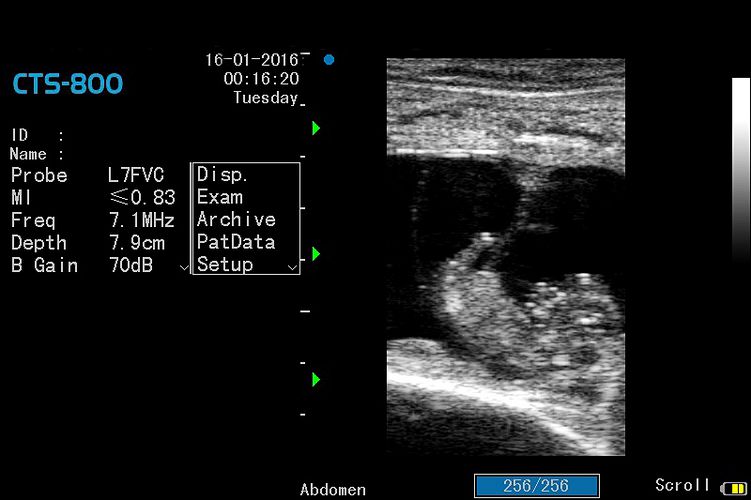

Ultrazvočna diagnostika brejosti